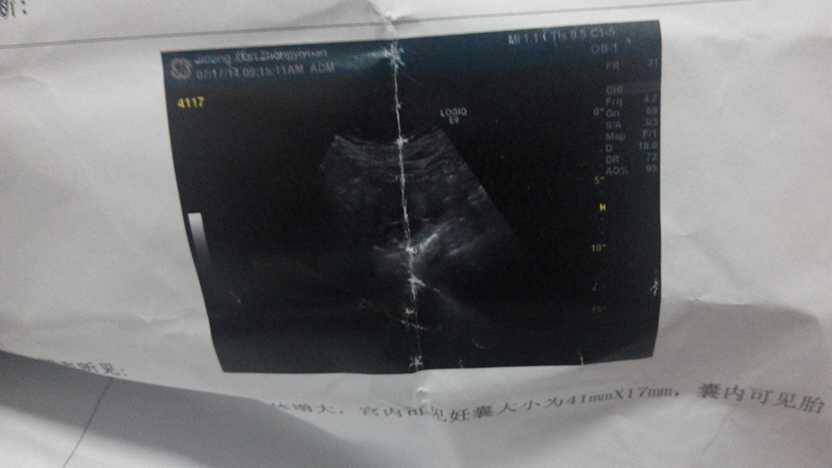

六十天去做的,是40乘以17 mm是男孩还是女孩? 六十天去做的,是40乘以17 mm是男孩还是女孩? 点击展开 陆雨琦妈妈 2014-07-21 07:48 为您推荐: 其他回答 我还没有去做了,人家说小等几天的。 二丫_nJn5 2014-07-23 17:07 我过两天去照,现在小今天才四十天。 二丫_nJn5 2014-07-23 07:07 谢谢你,很多人说不用紧张,这是宝作床,不是流产预兆,呵呵! 二丫_nJn5 2014-07-22 18:24 你怀孕有没有出血,我刚刚发现出血了,怎么搞的,怀孕才四十几天。 二丫_nJn5 2014-07-22 15:53 男孩可能性大。 二丫_nJn5 2014-07-22 15:34 加载更多 相关问题 怀孕45天左右胎囊是23 14 17 是男孩还是女孩 怀孕17周B超显示,可以看出是男孩还是女孩吗?正常吗? 怎么知道怀孕六十天是男孩女孩